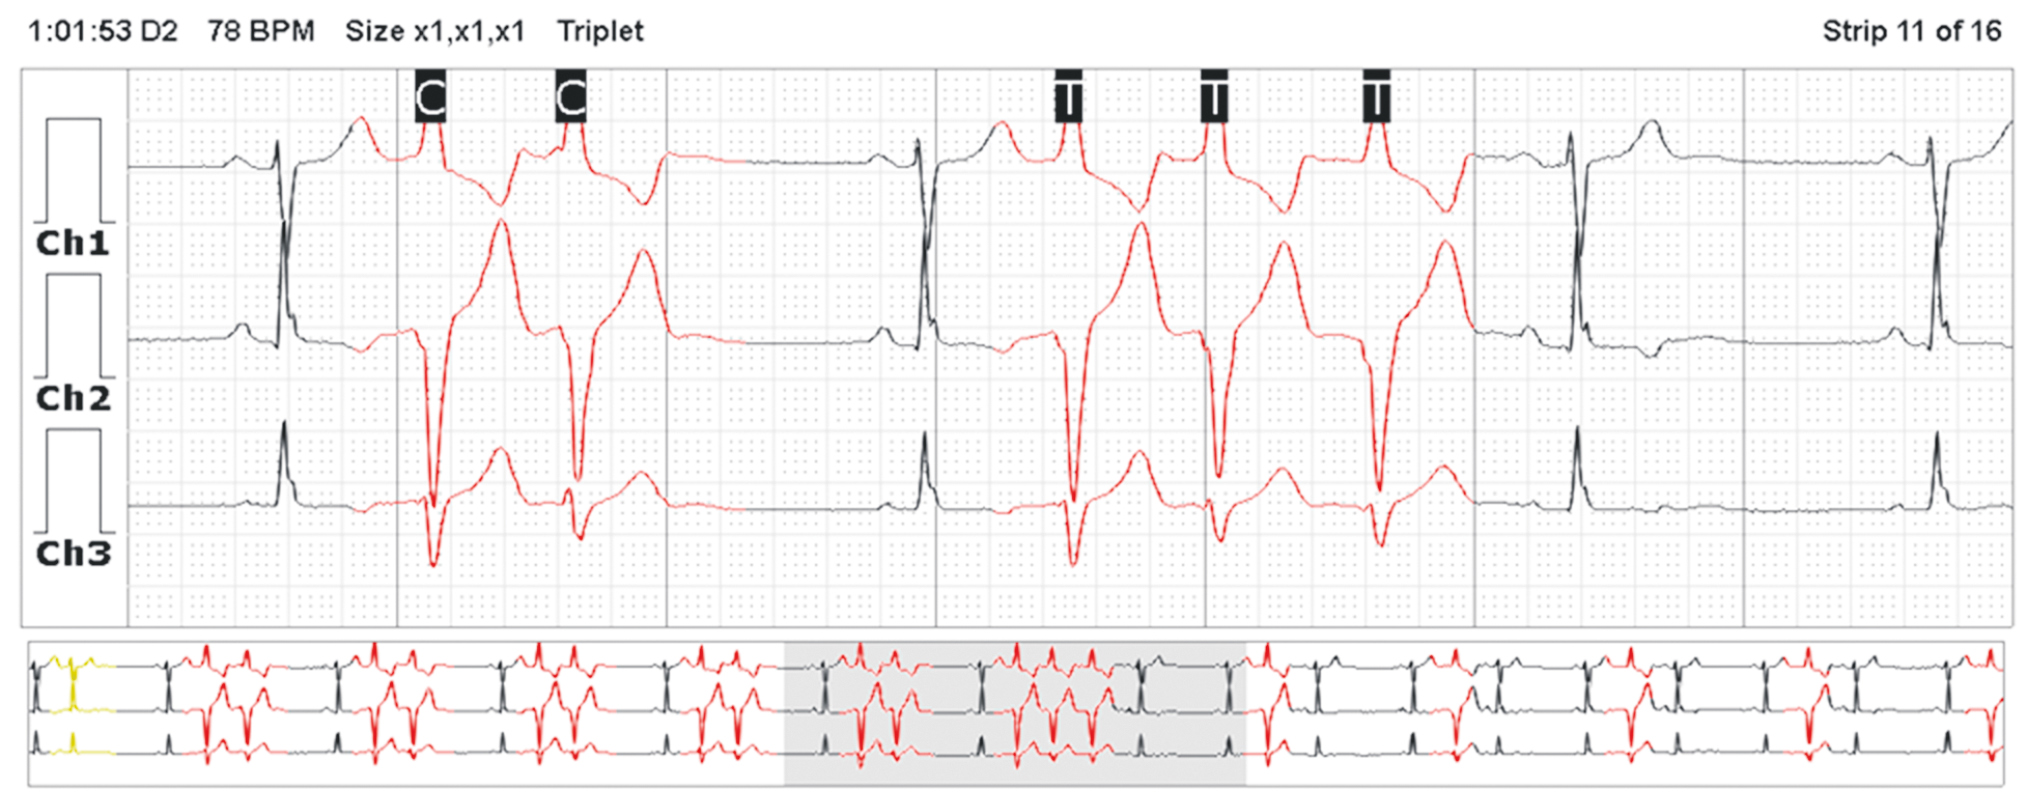

Multi-day ECG monitoring (154 h) was performed. single monomorphic premature ventricular complexes (PVCs) (54,529 [8.5%]) and paired (1,078 [2.1%]) and runs of monomorphic nonsustained ventricular tachycardia of 3–7 complexes (46 episodes in 154 h) were detected (Fig. 9).

Fig. 9. Fragment of multi-day electrocardiographic monitoring

Thus, the diagnosis of MVP and MAD was confirmed by instrumental methods of examination. No indications for surgical intervention were revealed at this stage. Ventricular arrhythmias requiring medical correction were registered. At the previous treatment stage, beta-blocker monotherapy (2.5 mg/day bisoprolol) was ineffective. Therefore, combined antiarrhythmic therapy was decided. Slow-release metoprolol succinate was recommended at a starting dose of 25 mg once daily in the morning, followed by dose titration, if necessary, in combination with 25 mg allaforte in the evening. During therapy, repeated 24-h ECG monitoring revealed no runs of nonsustained ventricular tachycardia and registered a significant decrease of number of PVCs from 8,520 in 24 h to 5,000 in 24 h. The patient is still being followed up.